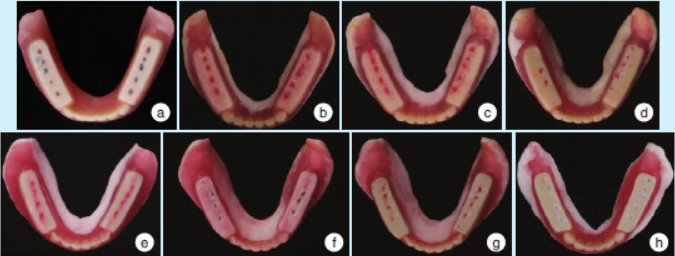

2.2义齿组织面、咬合印迹、哥特式弓描记图像和黏膜状态变化

治疗性义齿组织面呈现的变化规律:组织调理剂逐渐分布均匀,下颌义齿唇颊侧边缘向外扩展,舌侧适应性变化(图3)。咬合印迹变化:逐渐对称、均匀,呈明确的点接触,无早接触,无滑动(图4)。

图4 治疗前后义齿咬合印迹变化